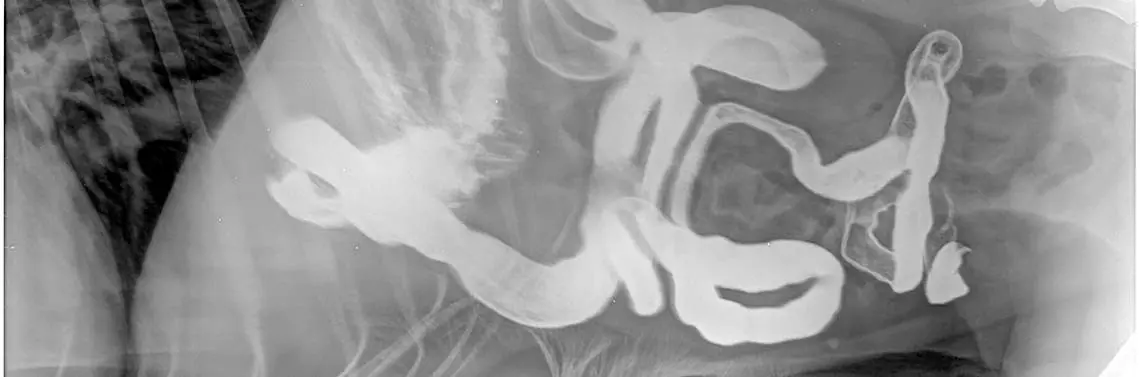

Narządy jamy brzusznej zostaną przedstawione głównie w obrazie ultrasonograficznym, który jest najczęściej wykorzystywany w typowym gabinecie weterynaryjnym. Anatomiczna grubość ściany prawidłowego jelita grubego, w porównaniu do grubości ściany jelit cienkich i żołądka, które w zależności od wielkości psa wynoszą ok. 3–5 mm (fot. 1 i ryc. 1), wynosi zaledwie 2 mm średnicy. Szerokość ich światła skłoniła niegdyś naukowców do oceny ich grubości poprzez wielkość – w rzeczywistości to jelita cienkie mają znacznie grubszą ścianę (fot. 2) [1, 2, 4, 7, 16, 17, 19, 20, 22].